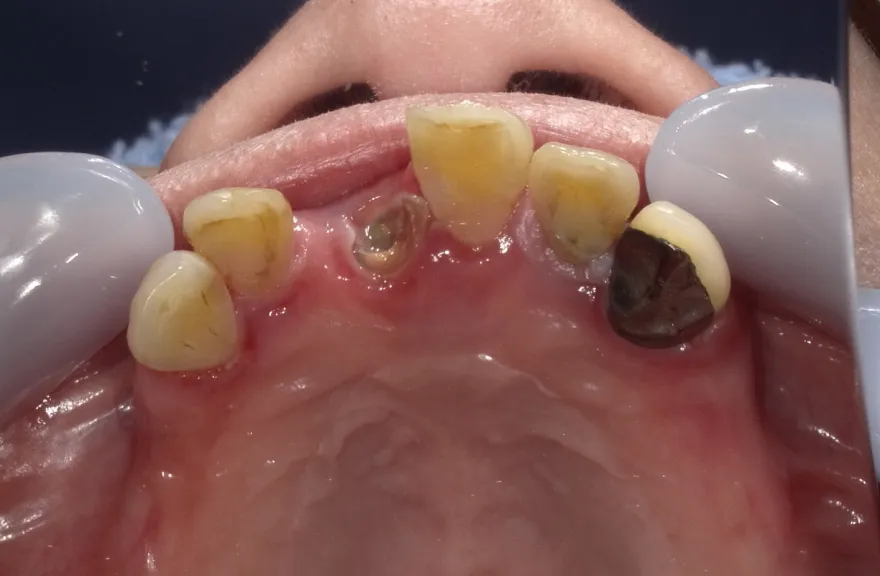

【治療例 3】奥歯が痛い、全体的にみて欲しい 60歳

今まで何回歯を入れてもトラブルが起きるために、奥の歯を入れないまま今日に至る、ということでした。

噛み合わせ・骨格を読み解き、今後の人生でトラブルが起きにくいように全体的な治療計画を練りました。 - 治療費用・方針

骨格の前後的な差がある方でした。術前のレントゲンより、上下で歯牙の損傷に明らかな差があるのがみてとれます。

上の歯がないところにインプラント治療を行い、上顎は全てインプラントフィクスチャーによる固定性の歯を入れられることも費用的には可能な方でした。

今回の症例では、敢えて上顎は総義歯形態をとり、骨格的な前後の差を解消するよう工夫しました。

上顎の残っていた歯も、差し歯としては使えずとも、敢えて根だけ残すことによって組織を温存し、義歯の安定に寄与するよう設計しました。